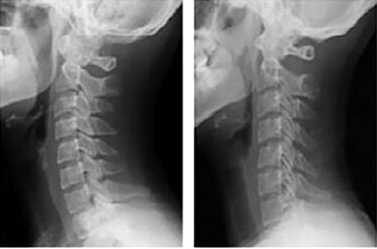

거북목은 머리가 어깨보다 앞으로 튀어나온 상태로, 측면에서 보면 거북이가 목을 내민 모습과 유사합니다. 경추의 곡선이 무너져 머리 위치가 앞으로 돌출되며, 어깨와 목에 큰 부담이 갑니다.

A. 경추의 곡선 변화와 머리의 위치 차이가 가장 큽니다. 일자목은 C자 곡선이 소실되었지만 머리는 정렬선 내에 있습니다. 반면, 거북목은 머리가 어깨보다 앞으로 돌출됩니다.